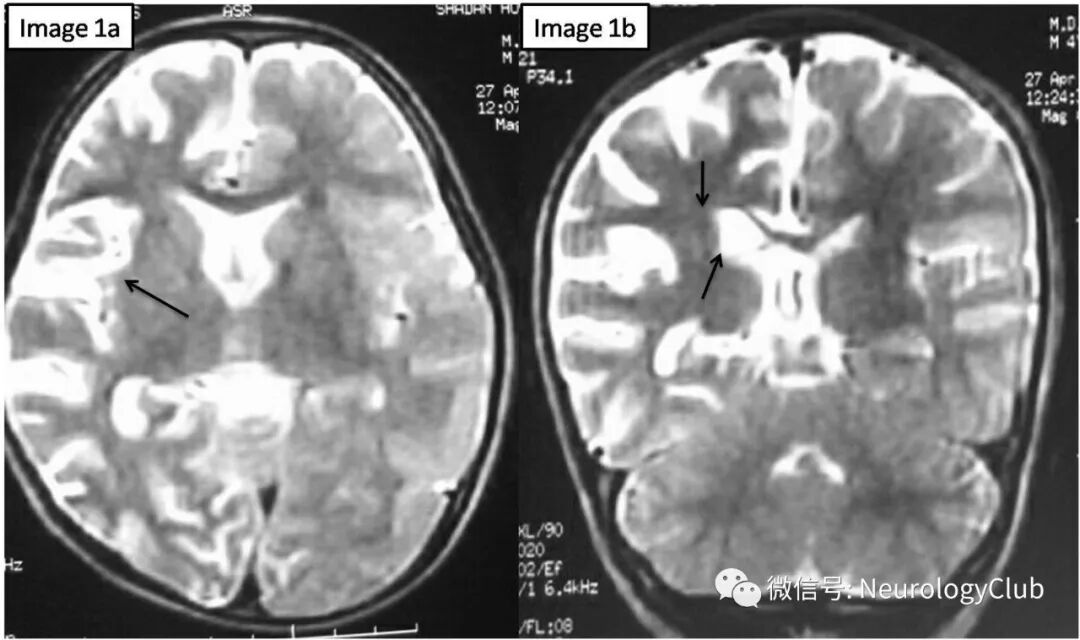

查体未见颜面部畸形或皮肤异常,高级认知功能缺损(记忆力,判断力,抽象思维和计算力),累及左侧面部和上下肢的部分性癫痫持续状态,左侧肢体无力,远端明显。未见其他不自主运动。视野检测提示同向偏盲。脑电图提示右侧半球为主的背景明显慢化。行头颅MRI检查,T2WI可见右侧脑沟增宽,右侧侧脑室扩大,右侧尾状核头萎缩(图1);T1WI可见类似表现符合右侧大脑半球萎缩(图2)。

(图1:a-b:T2WI可见右侧脑沟增宽,右侧侧脑室扩大,右侧尾状核头萎缩)